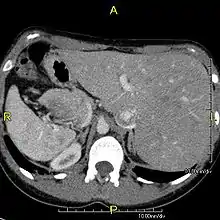

Primary ciliary dyskinesia (PCD) is a rare, autosomal recessive genetic ciliopathy, that causes defects in the action of cilia lining the upper and lower respiratory tract, sinuses, Eustachian tube, middle ear, Fallopian tube, and flagella of sperm cells. The alternative name of "immotile ciliary syndrome" is no longer favored as the cilia do have movement, but are merely inefficient or unsynchronized. When accompanied by situs inversus the condition is known as Kartagener syndrome.[1]

However, in some individuals with PCD, mutations thought to be in the gene coding for the key structural protein left-right dynein (lrd)[8] result in monocilia which do not rotate. There is therefore no flow generated in the node, Shh moves at random within it, and 50% of those affected develop situs inversus, which can occur with or without dextrocardia, where the laterality of the internal organs is the mirror-image of normal. Affected individuals therefore have Kartagener syndrome. This is not the case with some PCD-related genetic mutations: at least 6% of the PCD population have a condition called situs ambiguus or heterotaxy, where organ placement or development is neither typical (situs solitus) nor totally reversed (situs inversus totalis) but is a hybrid of the two. Splenic abnormalities such as polysplenia, asplenia and complex congenital heart defects are more common in individuals with situs ambiguus and PCD, as they are in all individuals with situs ambiguus.[14]

When accompanied by the combination of situs inversus (reversal of the internal organs), chronic sinusitis, and bronchiectasis, it is known as Kartagener syndrome[1] (only 50% of primary ciliary dyskinesia cases include situs inversus).